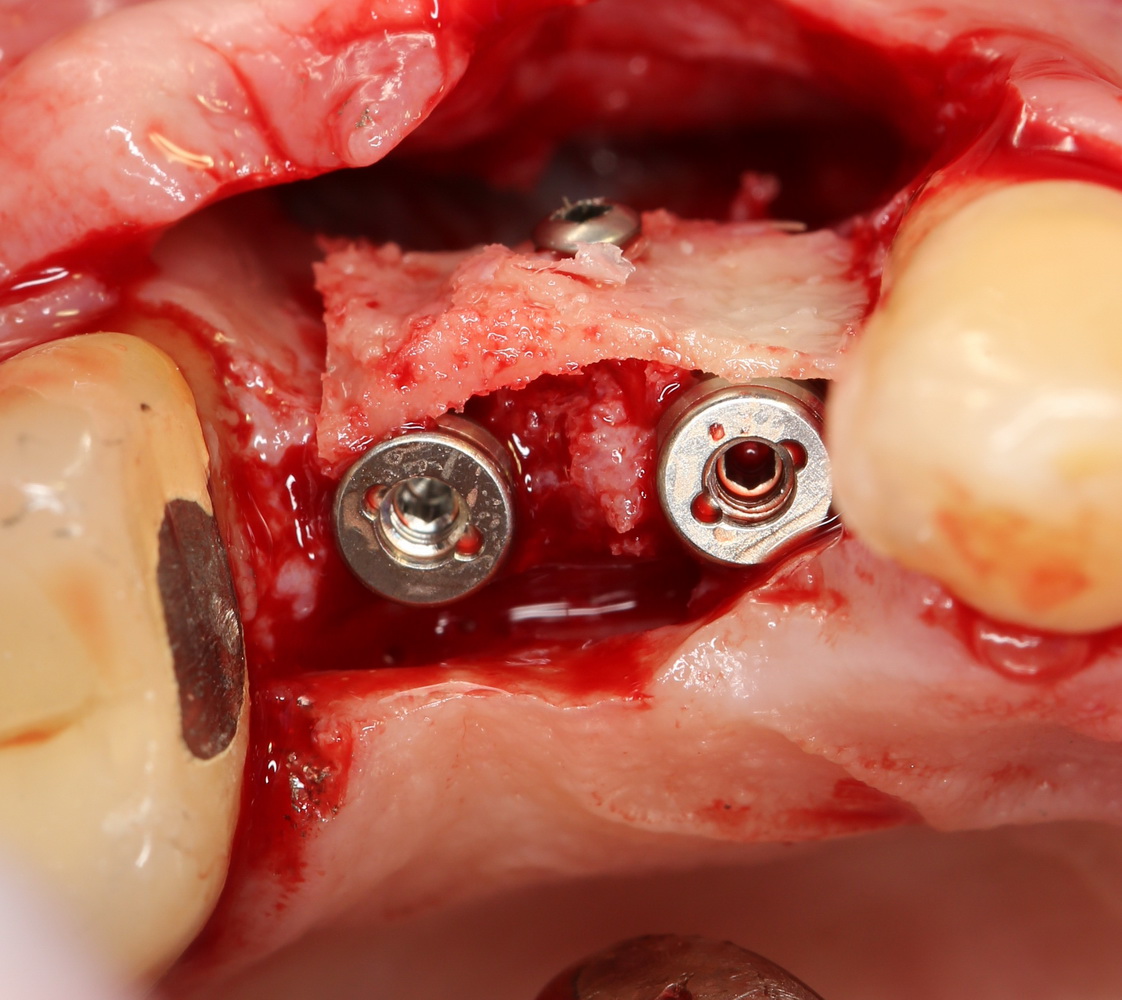

После установки второго импланта в правильное положение (ориентируемся по оси и форме лунки зуба), внешнюю кортикальную стенку восстанавливаем костным фрагментом, получившимся после синуслифтинга:

На деле — ничего сложного. Костный фрагмент просто фиксируется одним винтом. Таким образом восстанавливается отсутствующая костная стенка.

Субантральное пространство и пустые полости между костным блоком, имплантами и принимающим ложем заполняется аутокостной стружкой и закрывается мембраной BioGide:

Многих интересует вопрос — а для чего вообще нужны мембраны? Ну, с «искусственной костью» aka спейсерами всё более-менее понятно — их задача — восполнить и удержать заданный объем регенерируемой костной ткани. А какую роль играет вот эта белая тряпочка?

А все дело в том, уважаемые друзья, что различные ткани растут и регенерируют с разной скоростью. Если для регенерации слизистой оболочки или фиброзной ткани достаточно 1-2 недель, то костная ткань регенерирует дольше — от 1 до 4 месяцев. И, если мы не используем мембрану, слизистая оболочка быстро прорастает в те участки, куда просто не успевает прорасти костная ткань. Последней, естественно, расти уже некуда — и остеопластика теряет смысл. А коллагеновая мембрана ограничивает рост слизистой оболочки в тех участках, где ее не должно быть — тем самым, давая время на регенерацию костной ткани. Надеюсь, я понятно объясняю?))

В общем, друзья, при остеопластике аутокостной стружкой, биоматериалами, комбинированной (ламинарной) технике и даже в случае использования костных фрагментов нам нередко требуются эти самые коллагеновые мембраны. Их еще называют барьерными. Или мембранами «направленной регенерации».